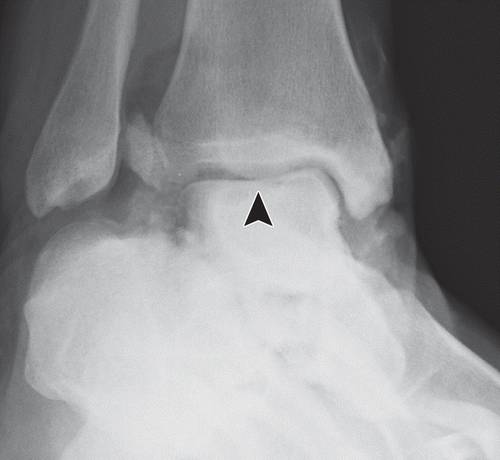

图11b外侧距骨软骨骨折。 (a)踝关节的AP射线照片显示外侧的距骨穹顶(箭头)的微妙的骨软骨骨折,被重叠的腓骨遮蔽。 (b)脚踝的斜位视图更好地显示骨折(箭头)。

图12a内侧踝关节骨软骨骨折。 AP(a)和斜位(b)踝骨的X线照片显示椎间融合器的移位骨软骨骨折(黑色箭头)。 还注意到倾斜的骨干腓骨骨折(箭头),syndesmotic加宽(双头箭头)和内侧清晰空间加宽(白色箭头b),符合syndesmotic和三角肌韧带复杂损伤的存在。